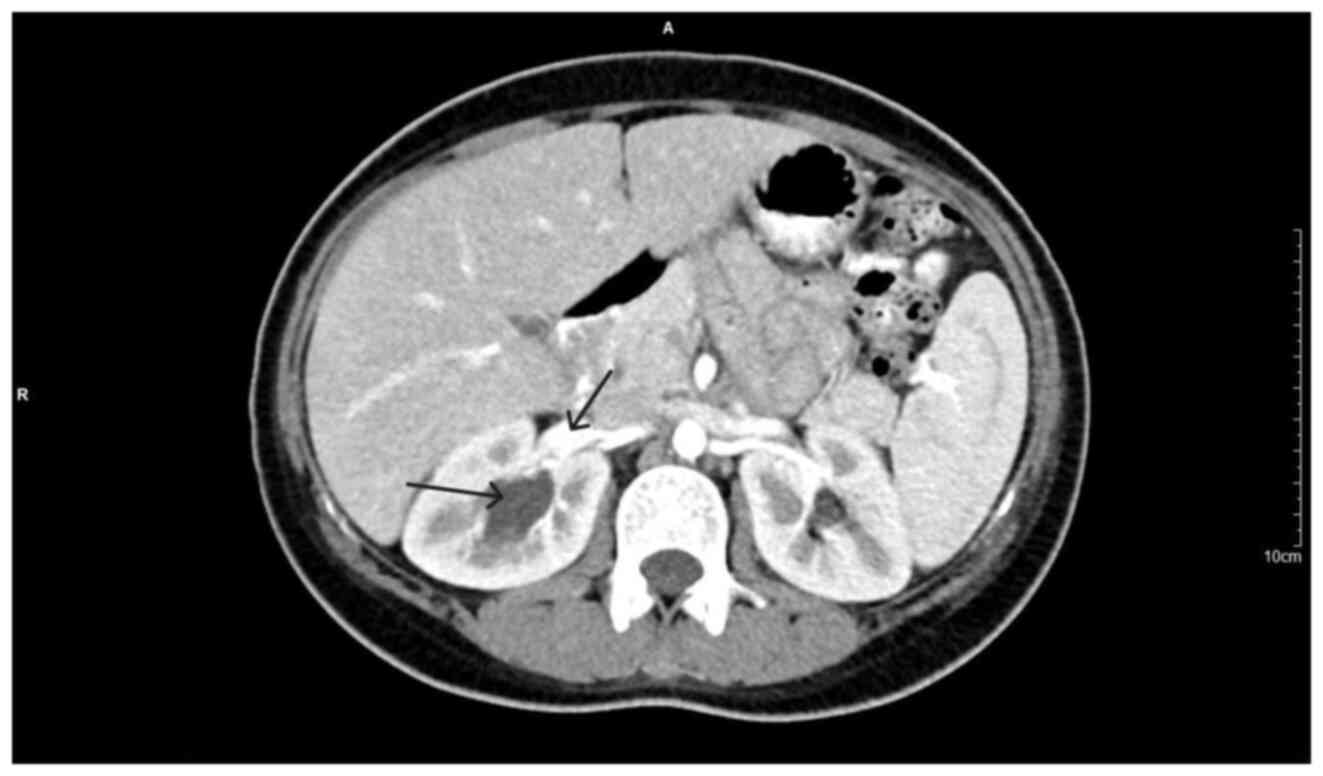

Large bladder flap haematoma following a caesarean section associated with right hydroureteronephrosis: A case report and a mini‑review of the literature

Post‑caesarean section bladder flap haematoma is a rare postpartum complication. There are currently no specific treatment protocols, at least to the best of our knowledge. In general, the failure of conservative treatment with antibiotics requires the re‑operation and surgical drainage of the haematoma. The present study describes the case of a primiparous pregnant woman who, at 40 weeks of pregnancy, delivered by caesarean section. On the 3rd post‑operative day, the puerperant, haemodynamically stable, developed febrile infection. During the evaluation, the presence of bladder flap haematoma associated with moderate right hydroureteronephrosis was found. The failure of conservative management led to the decision to perform a re‑laparotomy 1 week later. During the surgery, a large bladder flap haematoma was found with a retroperitoneal extension into the right parametrium. The surgical drainage of the haematoma and thorough haemostasis in the area of the vesicouterine pouch was performed. The patient was discharged from the clinic on the 5th post‑operative day following the re‑operation. After 2 weeks, an ultrasound revealed the complete repair of the lesions in the vesicouterine pouch and the right kidney. In the present study, a brief review of literature is also provided regarding the diagnostic and therapeutic management of patients with post‑caesarean section bladder flap hematoma.

Figure 4